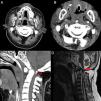

Mujer de 34 años. Antecedentes: encefalopatía anóxica perinatal, epilepsia, subluxación atloaxoidea con estenosis crítica de canal (fig. 1A), desestimada por neurocirugía en 2008 por riesgo quirúrgico. Sufre crisis comicial con traumatismo craneal, permaneciendo con cabeza en hiperflexión cervical. Atendida por el 112, en asistolia inicialmente, inician reanimación recuperando el pulso tras aislar vía aérea. En el hospital: TA: 80/50mmHg; FC 45lpm; SatO2 100% y 33°C. Se realiza TC total body en el que no se objetivan lesiones agudas y se describe subluxación atloaxoidea ya conocida (figs. 1B y C). En la UCI: tetraplejia, arreflexia, atonía de esfínter anal y ausencia de esfuerzo respiratorio en modo presión soporte en ventilador. En la RM se apreciaron lesiones compatibles con mielopatía aguda cervical (fig. 1D). Con diagnóstico de Spinal Cord Injury Without Radiographic Abnormality (SCIWORA), bajo perfusión de noradrenalina y pauta de dexametasona, la paciente no recuperó la actividad respiratoria.

A) Tomografía computarizada (TC) de 2008: corte axial a nivel de C1-C2 con estenosis de canal medular de 6mm (asterisco gris). B) Corte axial a nivel de C1 con estenosis de canal medular en TC en 2018 de 6mm (asterisco gris). C) Corte sagital en TC en la que se objetiva estenosis de canal en unión craneocervical ya conocida sin lesión aparente de partes blandas (flecha gris sin relleno). D) Resonancia magnética en secuencia T1: estenosis raquídea con engrosamiento dural difuso y alteración de la señal en región inferior de bulbo, así como intramedular cervical compatible con mielopatía traumática (flecha gris con relleno).